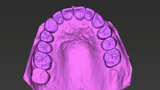

Compromised maxillary dentition treated with Straumann Pro Arch and a digital workflow